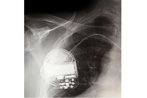

Using Non-Magnetic Capacitors For Medical Imaging Applications

MRI performance depends on strong, stable magnetic fields. Discover how non-magnetic multilayer ceramic capacitors with specialized terminations help preserve image clarity, meet medical and RoHS requirements, and support reliable MRI system operation.